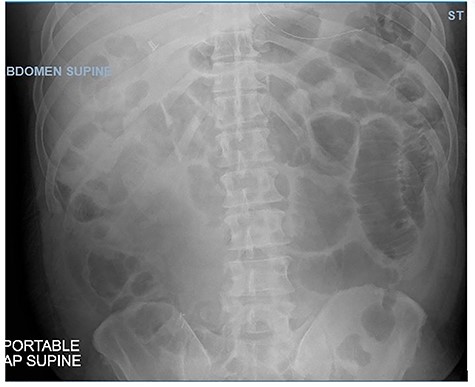

This case is a 54-year-old-male with past medical history of obesity, laparoscopic cholecystectomy, recurrent small bowel obstructions in 1997 and 2006 resolved with supportive care and COVID-19 infection in December 2020 who presented to the Emergency Department with nausea, non-bilious vomiting, non-bloody diarrhea and progressively worsening, sharp, diffuse abdominal pain for 1 week. On physical examination, he had diffuse abdominal tenderness. His white blood cell count was 3.8, consistent with his recent COVID-19 infection. Abdominal CT showed partial small bowel obstruction with a transition point in the right lower quadrant as well as fluid in the colon and throughout the bowel (Fig. 1). The patient had two episodes of bilious emesis overnight after his admission. A nasogastric tube was inserted and conservative management was attempted. The patient had persistently worsening abdominal pain, and was taken to the operating room for an exploratory laparotomy 2 days after admission.

CT abdomen/pelvis showing SBO with transition point in right lower quadrant.